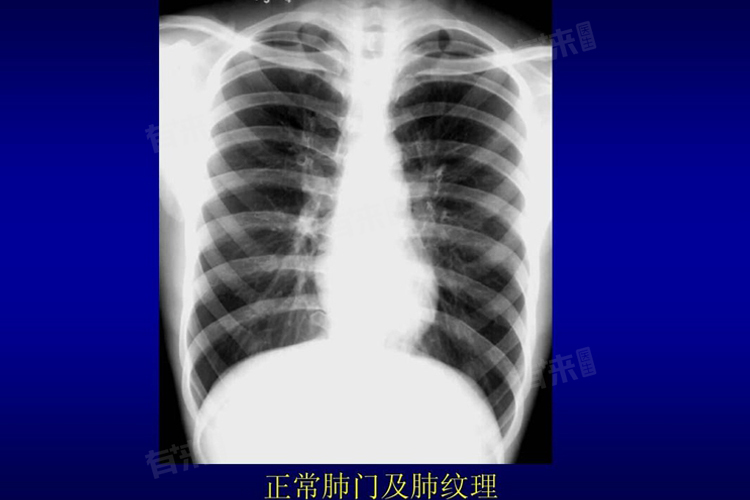

- 在CT影像上,条索影通常呈现为细线状或网格状的高密度影,边界相对清晰,与周围正常肺组织形成对比。放射科医生会根据其形态、分布及伴随的其他征象(如钙化、结节等)来判断其可能的来源。大多数情况下,单纯的条索影是良性的,不需要进一步干预,但如果伴随其他异常表现(如新发结节、磨玻璃影等),则可能需要结合临床病史进行更深入的评估。